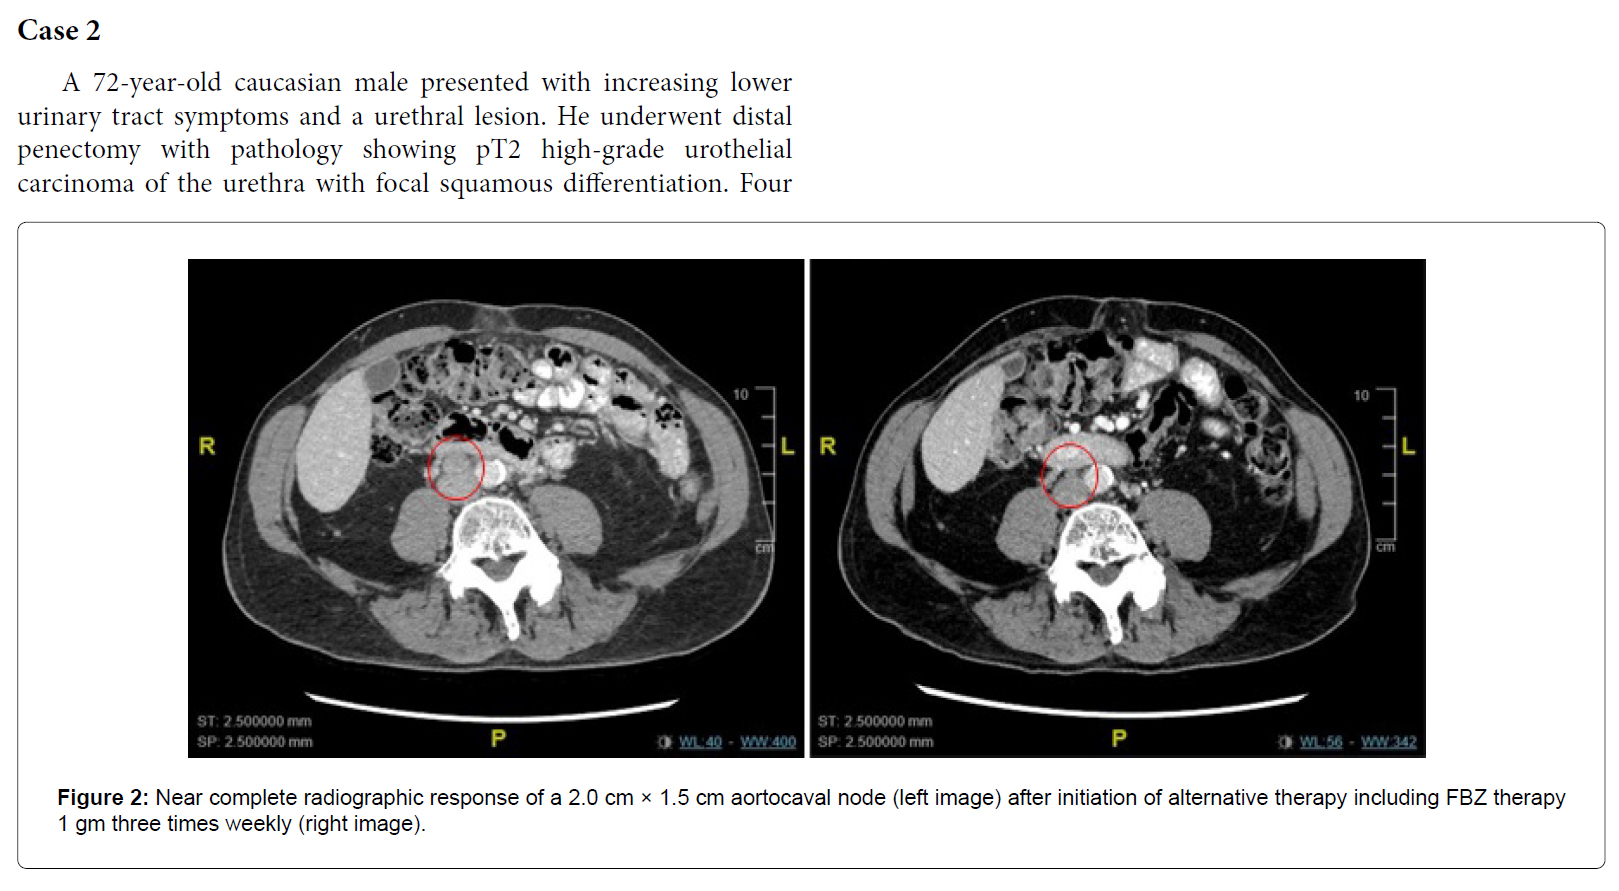

案例 2:72 岁男性,患有 4 期尿道尿路上皮癌,并出现肺、淋巴 结和脑转移。他接受放射治疗、卡铂、紫杉醇、帕博利珠单抗和 6 个周期的吉西他滨和顺铂治疗均失败

。开始每周 3 天口服 1000 毫克芬苯达唑、每天 800 毫克维生素 E、每天 600 毫克 姜黄素和 CBD 油CT 扫描显示 2 厘米主动脉腔静脉淋巴结转移的 肿瘤缩小直至消失(完全放射学反应)。

病例陈述案例 1 ...... ...... 讨论总之,我们有三名患有不同原发性泌尿生殖系统肿瘤的患者在接受 FBZ 治疗后表现出完全缓解。这提出了一个问题:FBZ 作为抗癌剂的效果如何,值得进一步研究。据我们所知,目前还没有类似的病例系列报道。 FBZ 属于一类微管不稳定剂,统称为苯并咪唑。破坏微管聚合以诱导有丝分裂停滞和促进细胞凋亡的能力是长春花生物碱的共同特征。FBZ 抗肿瘤特性的拟议机制包括抑制蛋白酶体活性、p53 活化、通过破坏微管蛋白产生细胞毒性以及下调对癌细胞存活至关重要的糖酵解酶 [ 1,4 ] 。其他苯并咪唑(如阿苯达唑)通过影响对 VEGF 表达和糖酵解的某些方面至关重要的 HIF- 1 -alpha 通路而具有抗肿瘤特性 [ 5 ]。这类药物发挥作用的机制多种多样,可能有助于通过靶向癌细胞存活的多种途径来限制耐药癌细胞系的增殖。 FBZ 已被安全地用作各种动物的抗寄生虫药,并可重新用于治疗人类恶性肿瘤。几种苯并咪唑类药物已显示出在人类身上重新利用的前景。一个例子是帕苯达唑,它已证明作为吉西他滨的补充疗法对胰腺癌患者有潜在疗效 [ 6 ]。病例报告显示,甲苯咪唑对转移性肾上腺皮质癌和转移性结肠癌患者有效,且副作用少 [ 7,8 ]。动物研究还显示甲苯咪唑和氟苯咪唑分别对多形性胶质母细胞瘤和血液系统恶性肿瘤有效 [ 9,10 ]。鉴于对多种恶性肿瘤具有高耐受性和适用性的证据,这值得进一步研究 FBZ 和其他苯并咪唑作为安全的化疗选择。 先前的研究表明,癌症对免疫检查点抑制剂(如 nivolumab)有反应,可作为 mRCC 的三线药物 [ 11 ]。治疗时间通常要长得多,中位治疗时间为 6 个月,三线治疗的总体反应率为 24%。我们的第一位 mRCC 患者可能仅使用 nivolumab 而不使用 FBZ 就获得了显著反应。然而,考虑到仅 1 个月的免疫检查点抑制剂治疗就获得了完全的放射学反应,FBZ 似乎也在诱导缓解方面发挥了重要作用。我们的患者在仅使用 FBZ 近一年且未进一步进行免疫检查点抑制剂治疗的情况下仍保持了长期缓解,这一事实支持了这一观点。 结论目前数据有限,关于 FBZ 抗癌特性的已发表研究很少。其他苯并咪唑类药物的研究范围更广,可以利用这些知识来帮助指导未来的 FBZ 研究,并评估此类药物的疗效,无论是作为单一药物还是联合治疗。鉴于 FBZ 的潜在益处以及似乎有限的毒性,有必要进行进一步研究,以评估这种药物可能有益的临床环境,并将其重新用于患有进行性生殖泌尿系统恶性肿瘤的患者,甚至可能用于其他恶性肿瘤。